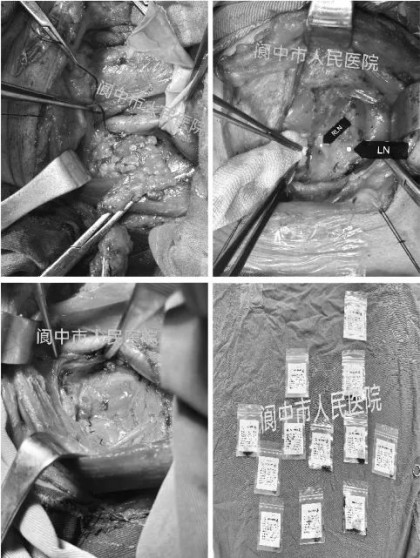

术中发现,患者左颈Ⅳ区转移性淋巴结肿大融合并侵犯颈内静脉,同时中央区淋巴结与喉返神经、食管粘连,手术较为困难。但唐涛博士团队迎难为上,在精心保护颈神经功能的同时,彻底清扫左颈Ⅱa、Ⅱb、Ⅲ、Ⅳ、Ⅴ区及中央区淋巴结,并细心从颈内静脉主干上完整剥离了长大的淋巴结,确保了颈内静脉的完整。整个手术过程顺利,患者术后恢复良好,未出现任何手术相关并发症,现已康复出院,按计划准备进行下一步放射性碘131治疗。